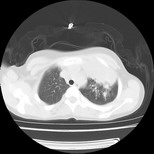

标题: PED3145:女,12岁,前期发热,咳嗽,无痰,CT右肺上叶实变 [打印本页]

标题: PED3145:女,12岁,前期发热,咳嗽,无痰,CT右肺上叶实变

女,12岁,前期发热,咳嗽,无痰,经头孢抗炎无效。ct右肺上叶实变影.5天后公布病理结果。以下是2010-2-13ct片

左前上纵膈可见大块影,与大血管关系密切,邻近肺少许炎症,考虑左前上纵膈占位,胸腺瘤或畸胎瘤,并左上肺膨胀不全。